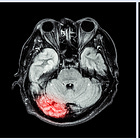

Critical Care 2024 Year in Review (Part 3)PREOXI, BLING III, ASTER, ANNEXA, GRECO, plus reviews on PPIs, TRALI, nutrition, morePulmCCMDec 20, 202414ShareNIV (BiPAP) for preoxygenation before intubation prevented hypoxemia and cardiac arrest (PREOXI trial)PulmCCM·June 16, 2024Read full storyTransfusion-associated lung injury (TRALI): ReviewPulmCCM·May 17, 2024Read full storyStress ulcer prophylaxis in the ICU: ReviewPulmCCM·June 22, 2024Read full storyNutrition strategies in critically ill patients: Review...·May 31, 2024Read full storyProtein targets for nutrition in critical illness: ReviewPulmCCM·June 3, 2024Read full storyContinuous antibiotic infusions for sepsis: do they save lives?PulmCCM·June 16, 2024Read full storyCan acetaminophen improve outcomes in sepsis?PulmCCM·June 3, 2024Read full storyWhich video laryngoscope is best for expected difficult airways?PulmCCM·June 9, 2024Read full storyWhat are time-limited trials in critical care?PulmCCM·June 10, 2024Read full storyAndexanet vs prothrombin concentrate complex for intracranial hemorrhage (ANNEXA-I trial)PulmCCM·May 18, 2024Read full storyCan a gut hormone protect the brain after cardiac arrest? (GRECO trial) PulmCCM·May 13, 2024Read full storyHow bad are outcomes after transfer to LTACH?PulmCCM·June 16, 2024Read full storyThrombectomy proves beneficial for the largest ischemic strokes, too (LASTE trial)PulmCCM·May 12, 2024Read full storyPreviousNext